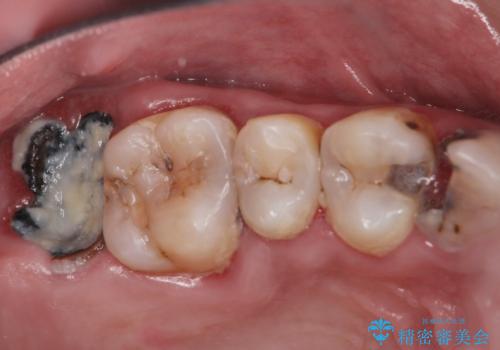

- 口の中をマスク生活の間に全て治したい、見た目を良くしたいとの事で来院。

まず徹底的に虫歯を取り除き、保存が出来ない部位は抜歯(親知らずを含む)を行い、根管治療が必要な部位は精密根管治療を行いました。

その後、インプラント治療、セラミック治療を行いました。

一度治療するはを全て仮歯に変えて、歯茎を整えてからセラミックを装着しました。

また、虫歯が歯肉の中まである場合はAPF(歯肉弁根尖側移動術)も行なっています。